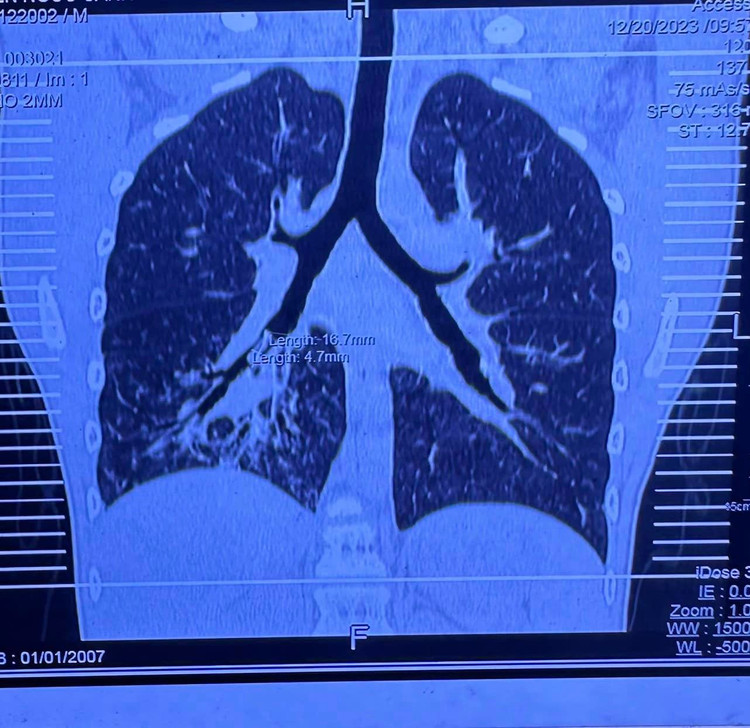

Thời gian sau bé về quê khám tại BV chuyên lao và bệnh phổi Bình Định, tại đây chụp CT Scan phổi lại nghi dị vật đường thở nên người nhà xin chuyển BV Nhi Đồng 1 nội soi đường thở.

| Một số hình ảnh phim Xquang, CT ngực, hình qua nội soi đường thở và dị vật gắp được |

Ngày 25/12, ekip phẫu thuật của khoa Tai Mũi Họng BV Nhi đồng 1 đã sẵn sàng cho ca dị vật khó và hy hữu này, vì đây là 1 trường hợp dị vật nằm trong phổi quá lâu và rất sâu ở phế quản hạ phân thùy phổi bên phải.